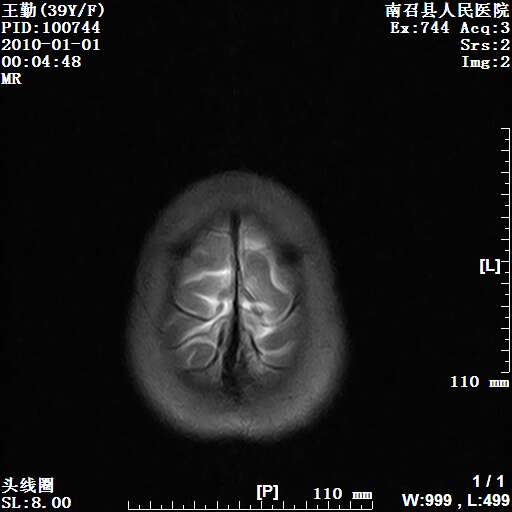

以下是引用随光逐影在2010-1-22 9:03:00的发言:[br]考虑左侧中颅窝(蝶骨翼区)脑膜瘤侵犯蝶骨翼并突入左侧眼眶。

以下是引用水过无痕在2010-1-22 14:55:00的发言:[br]一、定位:颅外占位;二、定性:恶性可能性大;三、组织来源:来源于左侧眼外直肌或其他部位;考虑为:横纹肌肉瘤>转移瘤>脑膜瘤.